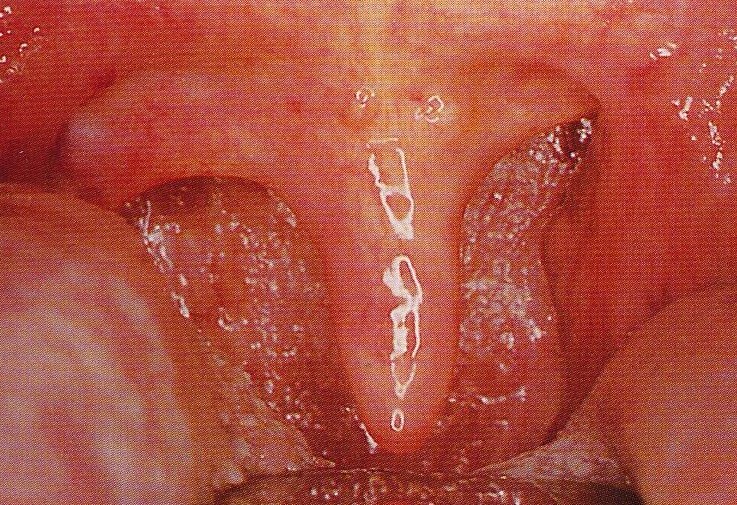

慢性咽炎的症状

南京耳鼻喉科医院咽喉科医生:咽喉疼是一种常见的病症,它多发于感冒、扁桃体炎、鼻窦炎、咽喉炎以及病毒感染通常都伴有咽喉痛。多数急性咽喉痛通过消炎治疗会在数天至数周内自动消失,然而,如果疼痛持续存在或在几天内加重,则需要通过专业的检查进行确诊和治疗了。